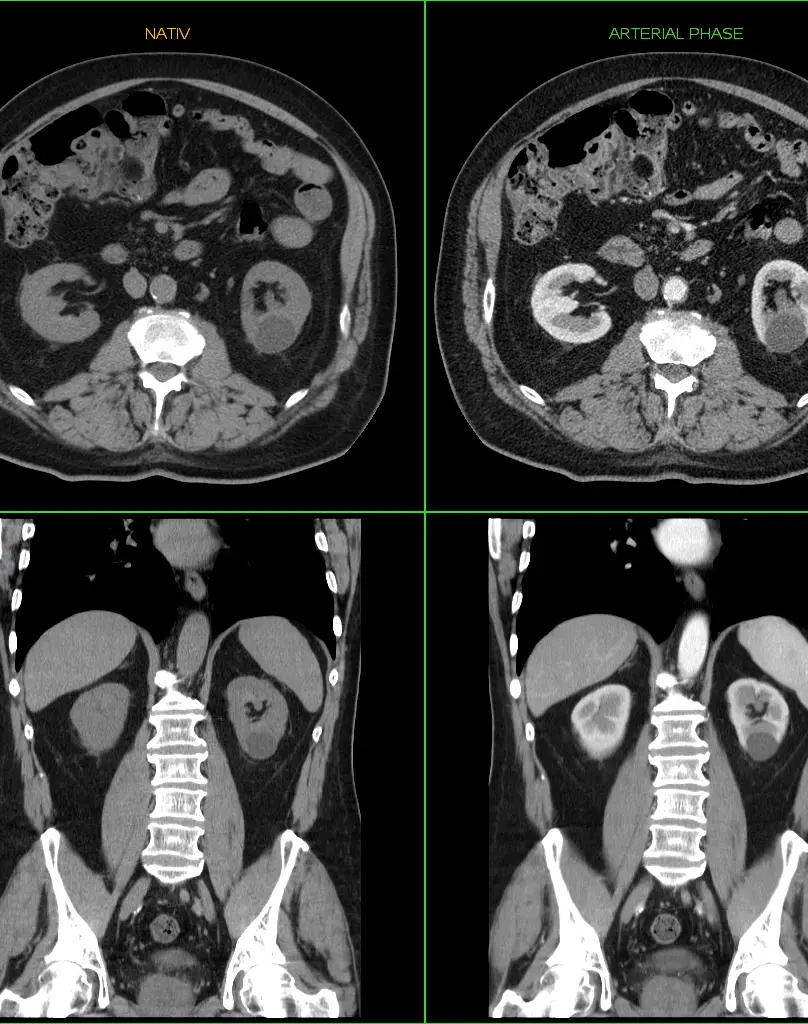

Контрастное усиление (за 1 зону)

Это методика улучшения визуализации тканей и сосудов с помощью внутривенного введения специального вещества, усиливающего контрастность изображений. Чаще всего применяются препараты на основе гадолиния (редкоземельных металлов), которые безопасны и хорошо переносятся пациентами.

Для введения контрастирующего вещества (КВ), заранее устанавливается внутривенный катетер. КВ вводится лаборантом (медсестрой) после завершения стандартных сканов. Время постконтрастных сканов около 5 минут.